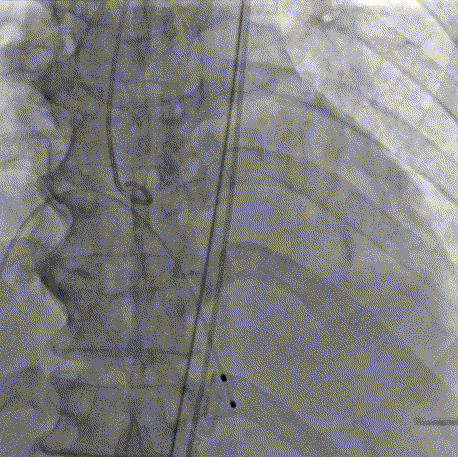

手术过程

术前主动脉根部造影

20mm球囊预扩

AV26瓣膜定位

AV26瓣膜工作位造影

AV26瓣膜释放

术后主动脉根部造影

本例手术为重度钙化二叶式病变重度主动脉瓣狭窄TAVR手术,团块状钙化挤压存在移位瓣周漏风险,术前手术团队对患者进行了全面细致的评估,确定假体瓣膜锚定区域范围,制定术前释放策略。何柳平主任团队通力配合、精准释放,充分利用TaurusElite可回收功能,在瓣膜释放至2/3时,多角度评估瓣膜植入深度、锚定力以及冠脉灌注情况,确认瓣膜植入深度合适、锚定力稳定,缓慢逐个脱钩,进行瓣膜释放。释放后造影显示瓣膜膨胀良好,行血流动力学评估,跨瓣压差从术前100mmHg降至15mmHg,少量瓣周漏,手术圆满完成。